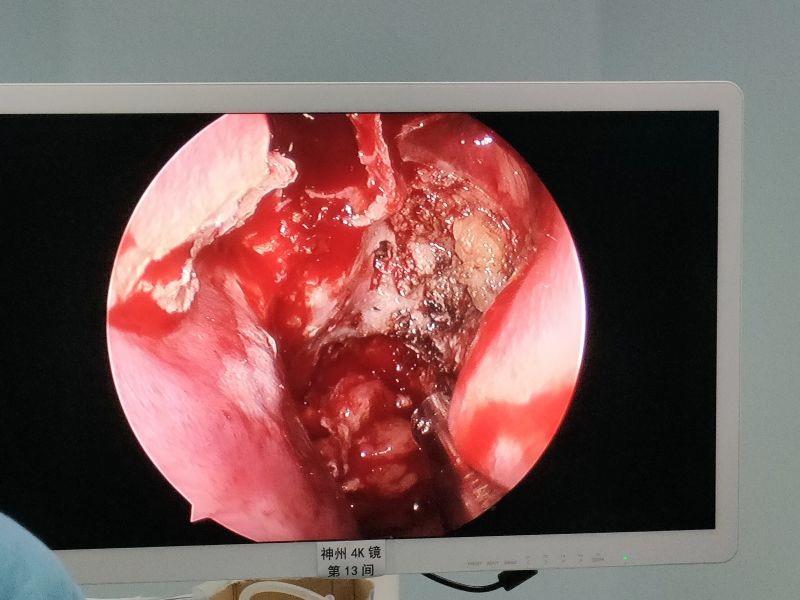

手术进行中 医院供图

手术视野 医院供图

随后,耳鼻咽喉头颈外科主任医师黄金忠和副主任医师孔令平默契配合,在麻醉科主任医师陆永红的帮助下成功为小廖进行了鼻内镜下鼻咽纤维血管瘤切除手术。